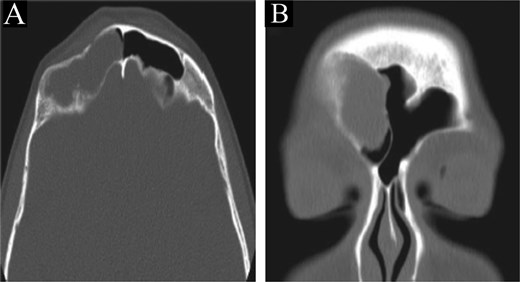

This is a 14-year-old female, with no significant medical or surgical history, who presented to our otolaryngology clinic complaining of right frontal bone depression associated with headache for one month, with no other ENT-related symptoms. Physical examination and nasal endoscopy were unremarkable.

A CT scan of the paranasal sinuses showed a low-attenuation lesion in the right frontal sinus lateral aspect with thinning and resorption of the sinus walls and depression in the posterior side of the anterior wall, suggestive of a depressed fracture (Fig. 4). MRI of the brain and paranasal sinuses showed no thickening of the meninges and no intracranial extension.

CT scan of the brain and paranasal sinuses in (A) axial and (B) coronal views, showing a lesion in the right frontal sinus with resorption of posterior and lateral walls. The anterior wall shows a depressed fracture.

The patient underwent image-guided ESS with frontal sinusotomy. A 45-angled endoscope helped in recognition of the mucocele, which was treated with marsupialization (Fig. 5). The thick anterior inferior wall was removed. During 2 years of follow-up, no recurrence or complication was observed.